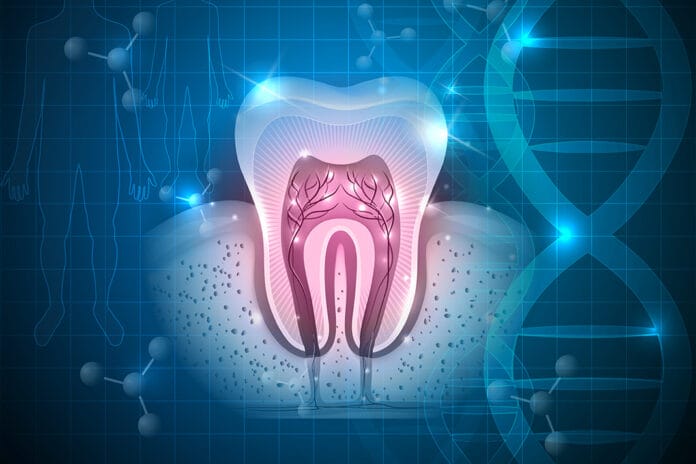

Research Shows Panoramic Radiographs’ Ability to Diagnose Bruxism via Bone Remodeling

Patients who experience bruxism, or teeth grinding and clenching, often suffer from jaw pain, tooth sensitivity, headaches, and other symptoms. A diagnosis usually starts...